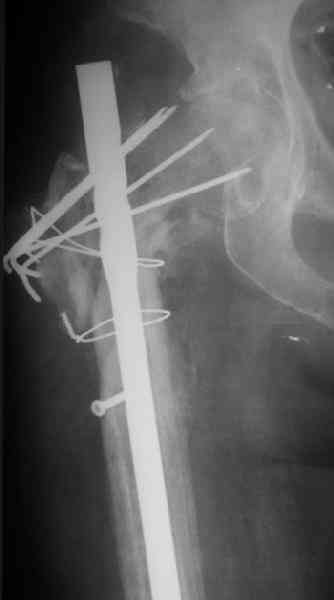

Поступила женщина 62 лет. В X 2006 оперировна в одной из горбольниц, по поводу, видимо, оскольчатого подвертельного перелома.

Почему сделан такой странный остеосинтез - пока неизвевстно. 3 мес. в тазобедренной гипсовой повязке. Картина через полгода после операци, в апреле - первый снимок. После этого снимка убрали винт, проникающий в сустав. Картина на сегодня - следующие 2 снимка.

Dear All,A female 62 y.o. referred to our unit. In X 2006 was operated somewhere - open reduction and fixation of a fragmented subtrochanteric fracture. Why so strange fixation was performed - no data at the moment. 3 month in plaster cast. Image 1 - Apr 2007, 6 month after the surgery. The screw was removed some days later.

Other images present the current situation.

Wound healed uneventfully. Now there is local hyperemia at the lateral side of the proximal femur. WBC - 6.2, ESR - 48 m/h.